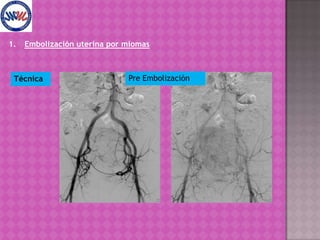

La embolización uterina por miomas fue desarrollada en Francia y su primera publicación internacional fue en 1995. Es un tratamiento seguro y eficaz, con bajas complicaciones y resultados comparables a la cirugía tradicional, con ciertas contraindicaciones absolutas y relativas. Se puede repetir y no impide futuras cirugías si es necesario.